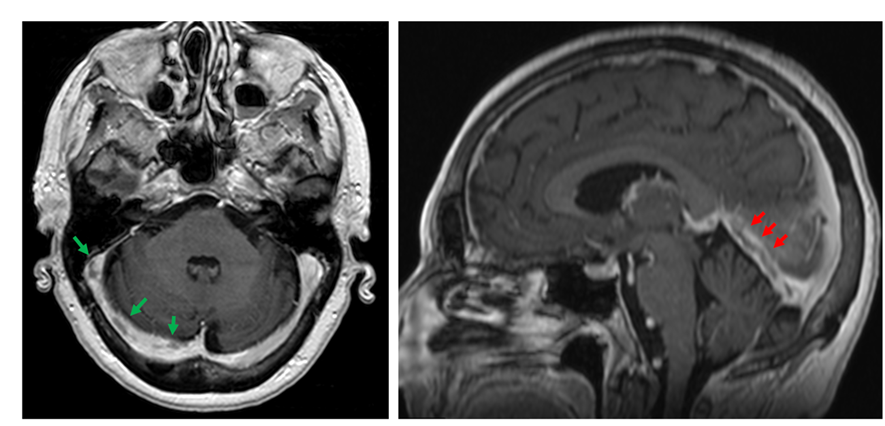

A brain MRI study displayed an extensive CVST, with main involvement of the right transverse and sigmoid sinuses (Figure 1), and extension to the straight sinus and vein of Galen. There were infarction signs in the thalamus (Figure 2) and in the right occipital region, with associated bleeding in this zone (Figure 3).

Fig. 1 MRI T1-weighted images with contrast. Filling defects in the transverse and sigmoid venous sinuses (green arrows, axial view). Lineal filling defect in the straight venous sinus (red arrows, sagittal view).